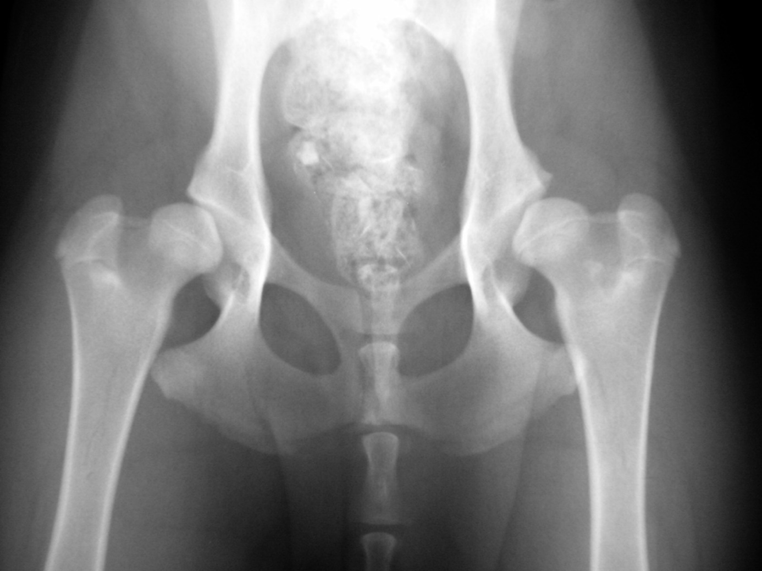

Abb. 4: 8 Monate alter Mischlingshund mit hochgradiger HD (Grad E). Der Kopf ist kantig, oben abgeflacht und weitgehend aus der Pfanne herausgerutscht, die Pfanne selber oben stark abgeflacht, sogar fliehend. Am Vorderrand der linken Pfanne (im Bild rechts) hat sich eine Randzacke ausgebildet, ein untrügliches Zeichen von schwerer Arthrose.

Abb. 5: Derselbe Hund im Alter von 5 Jahren. Die Oberschenkelköpfe sind nun hochgradig verformt und berühren die Pfannen nur noch knapp. Die Oberschenkelhälse sind massiv verdickt und verformt, die Morganlinien sind als breite Knochenleiste erkennbar. Beide Pfannen sind stark abgeflacht und haben insbesondere rechts hochgradige arthrotische Zubildungen entwickelt.